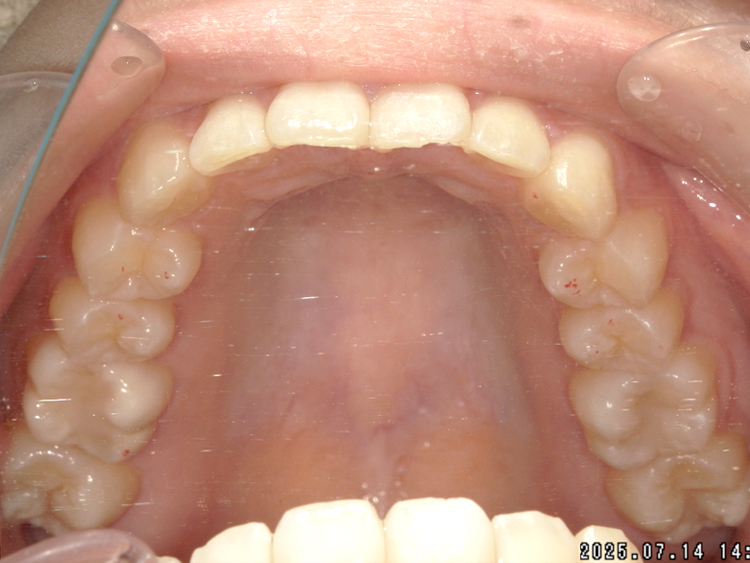

症例4

Before

After

| 主訴 | 上下前歯のがたつき |

|---|---|

| 年齢 | --- |

| 治療 期間 |

約9ヶ月 |

| 治療 内容 |

インビザラインiGoで上下顎の治療。 |

| 治療費 | ¥550,000(税込)/調整料含む |

| 治療のリスク | 矯正終了後は、リテーナーを指示通りに使用し、歯の後戻りを防ぐ必要があります。 |